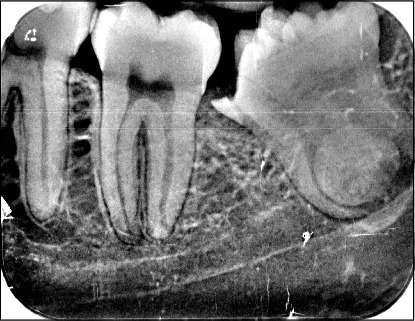

Introduction: Gemination and fusion are rare developmental anomalies that can present significant diagnostic challenges. Due to the complexity of distinguishing between these conditions, the term "double tooth" is commonly employed in clinical practice. The precise etiology of these anomalies remains uncertain, and their occurrence in permanent dentition-particularly involving molars-is exceptionally rare. This report describes an uncommon case of gemination affecting the mandibular left third molar (tooth 3.8) and provides a comprehensive discussion contextualized within existing literature. The case report was prepared following the CARE guidelines to ensure methodological rigor and completeness. Methods: After an intraoral examination and radiographic assessment-including orthopantomography, periapical radiographs, and cone beam computed tomography (CBCT)-the patient underwent surgical extraction. The procedure involved administering a truncal nerve block to anesthetize the inferior alveolar and lingual nerves, supplemented by local infiltration anesthesia of the buccal nerve. A full-thickness mucoperiosteal flap was elevated, followed by ostectomy and odontotomy to facilitate extraction. The tooth was subsequently removed using a combination of elevators and forceps. Results: Postoperative evaluations conducted at 1.5 and 3 months confirmed complete healing of the surgical site. A detailed analysis of pre- and postoperative radiographic and clinical findings validated the diagnosis of gemination, characterized by coronal continuity with a single root and root canal. Conclusions: Gemination of third molars is exceedingly rare, with only a few cases documented in the literature. To the best of our knowledge, this is the first reported instance of gemination involving the mandibular left third molar (tooth 3.8). This report contributes to the growing body of knowledge on developmental dental anomalies and highlights the importance of thorough differential diagnosis in similar clinical scenarios.

Abstract Image